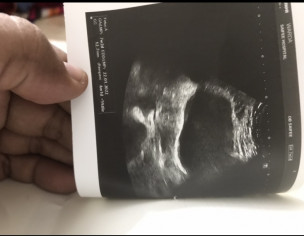

Ultrasound attached.

- In which week my wife is?

- Pls suggest what to do? Is it pregnancy or not?